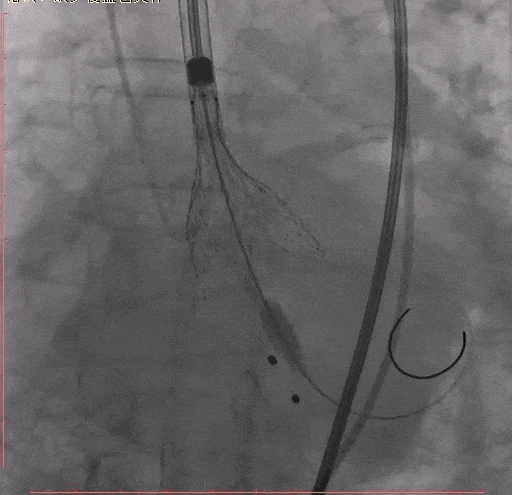

Step 7. Taurus 26 瓣膜释放至工作位造影确认位置

Step 8 Taurus 26 瓣膜释放后造影

Step 9. 患者出现心衰,血流动力学不稳,予以IABP植入

术后复查超声心动图:人工瓣膜功能正常,主动脉瓣峰值流速179m/s,平均压差7mmHg,未见瓣周漏。